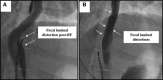

Methods: In 10 animals, under general anesthesia, the lower esophagus was deflected toward the inferior vena cava using an esophageal deviation balloon, and ablation was performed from within the inferior vena cava at areas of esophageal contact. Four discrete esophageal sites were targeted in each animal: 6 animals received 8 PFA applications/site (2 kV, multispline catheter), and 4 animals received 6 clusters of irrigated RFA applications (30 W×30 seconds, 3.5 mm catheter). All animals were survived to 25 days, sacrificed, and the esophagus submitted for pathological examination, including 10 discrete histological sections/esophagus.

Results: The animals weight increased by 13.7±6.2% and 6.8±6.3% (P=0.343) in the PFA and RFA cohorts, respectively. No PFA animals (0 of 6, 0%) developed abnormal in-life observations, but 1 of 4 RFA animals (25%) developed fever and dyspnea. On necropsy, no PFA animals (0 of 6, 0%) demonstrated esophageal lesions. In contrast, esophageal injury occurred in all RFA animals (4 of 4, 100%; P=0.005): a mean of 1.5 mucosal lesions/animal (length, -21.8±8.9 mm; width, -4.9±1.4 mm) were observed, including one esophago-pulmonary fistula and deep esophageal ulcers in the other animals. Histological examination demonstrated tissue necrosis surrounded by acute and chronic inflammation and fibrosis. The necrotic RFA lesions involved multiple esophageal tissue layers with evidence of arteriolar medial thickening and fibrosis of periesophageal nerves. Abscess formation and full-thickness esophageal wall disruptions were seen in areas of perforation/fistula.